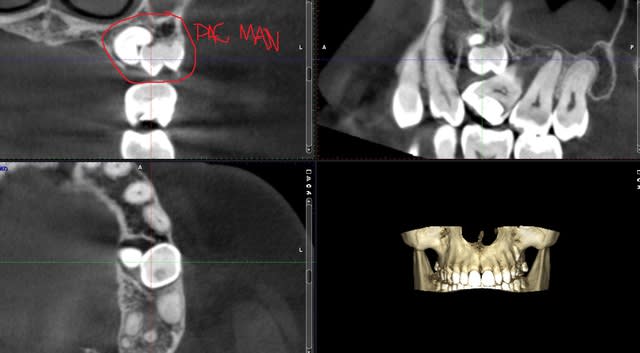

25 est en palatin ou vestib? Seule la cbct peut donner une idée de la stratégie, amha.

Cbct, proximité artère palatine si 25 en palatin, pas évident..

Bien sûr que le cbct est prévu.mais ma question est plus: y a t il une réelle nécessité d'extraire 25..

Extraire 65 dans tout les cas et 25 suivant ce que dit le CBCT.

Mon traitement idéal serait virer la 65, voir pour virer la 25. Multiattaches pour réorganiser le secteur antérieur et amener la 26 à sa place. Ce qui libérera l'espace pour un implant en place de 25.. Elle passe son cbct lundi.

revu la patiente hier.

je mets en pj le scan.. la 65 est vestibulaire, je vais la sortir. je n'ai pas envie de toucher la 23 super haute et très palatine.

Si tu lui braque le germe, elle va en faire de l odf, vu que rien ne s opposera à l' enfoncement de 26, avec création d une poche paro, douleur et inflammation , donc perte tissulaire associé.

Si pas d odf, pas d 'extraction, sinon tu contrôle plus rien.

Pourquoi tu dis que la 23 est incluse? pour moi c est 25 qui est horizontale, au dessus un germe surnuméraire et 23 sur l 'arcade , non?

Oui 25 incluse, faute de frappe de ma part.

Il y a deja une poche paro avec soucis inflamm à répétition .. d'où la décision d'extraire 65